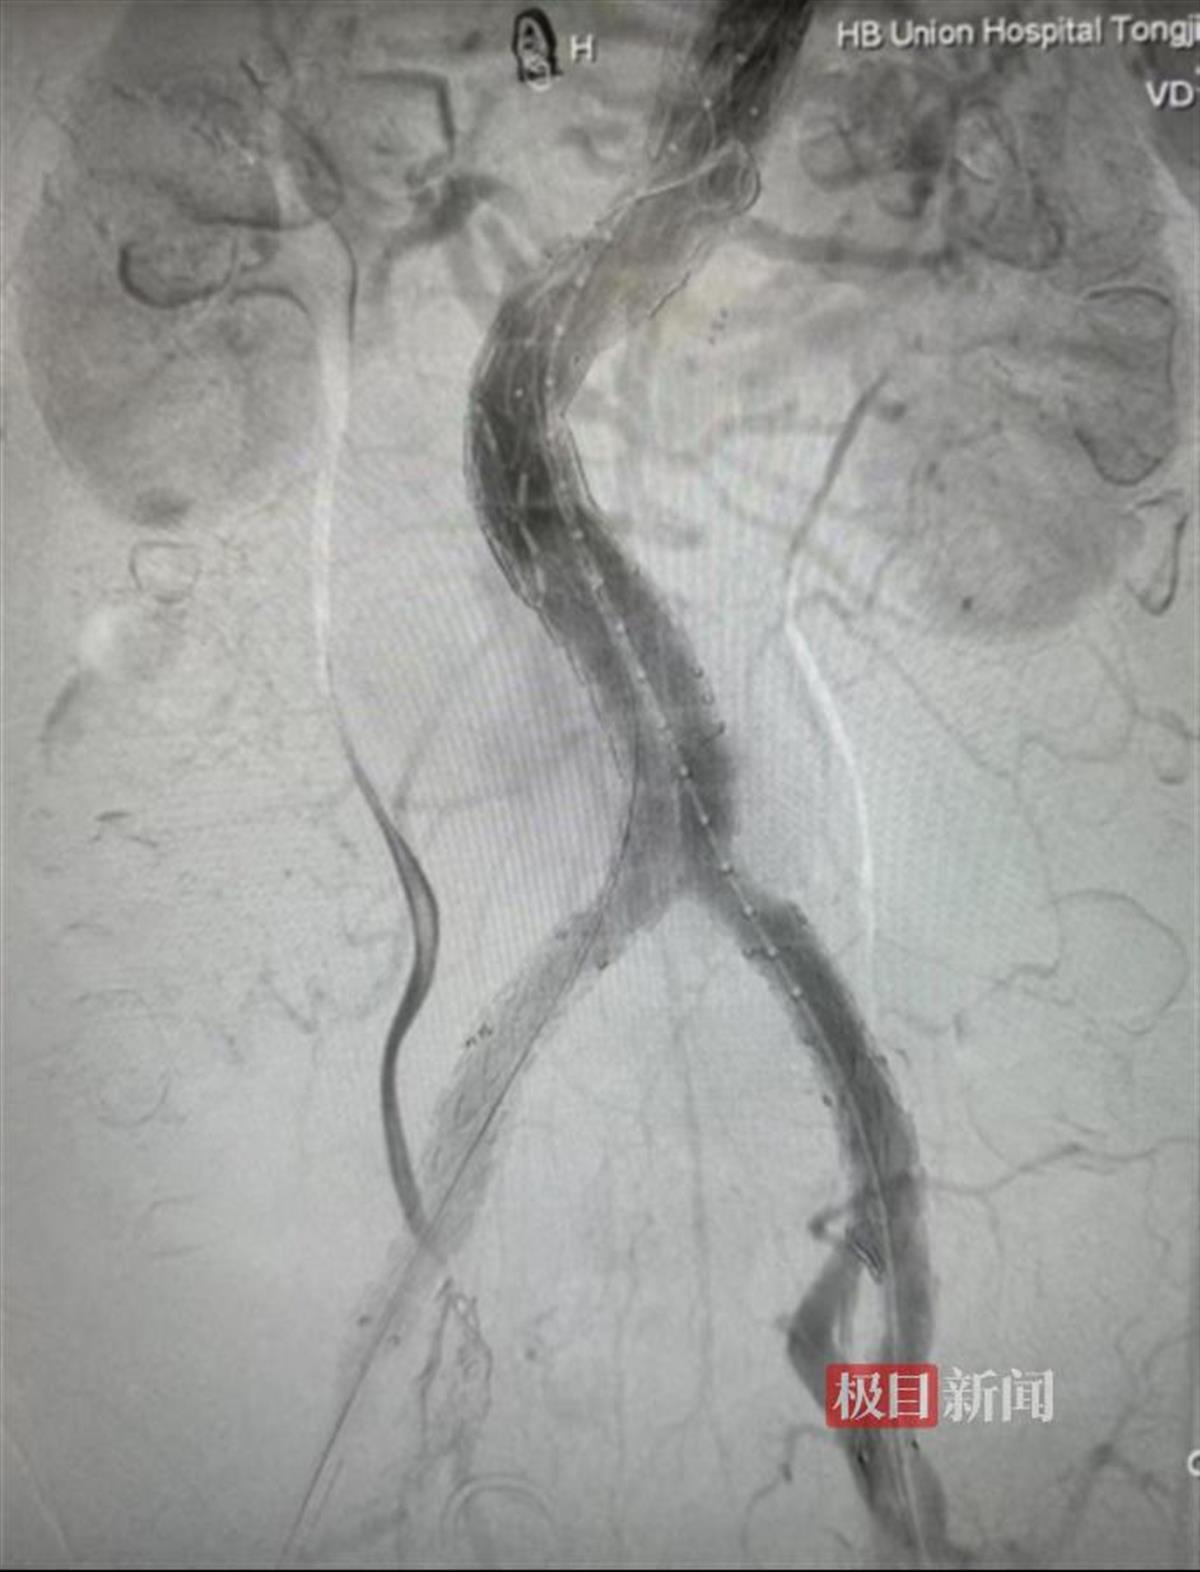

支架置入后夹层消失,分支血流通畅

手术包括体外改装支架和腔内支架置入两大环节。首先需要在体外将支架改装,即在主动脉支架上按照术前测量的数据进行开窗,部分分支需要在“窗口”上缝合内嵌或外嵌分支,再将改装好的主动脉支架重新收回输送器。根据术前计划建立好通路,将改装好的支架送入患者体内后,再经支架内分别选入预开的四个窗口,并进入患者的分支动脉,并接入桥接支架来保证上述分支动脉的正常血流。经过5小时的手术,终于按照预期隔绝了破裂的腹主动脉夹层动脉瘤,同时各分支动脉血流通畅,保证了重要脏器的血供,手术效果非常理想。